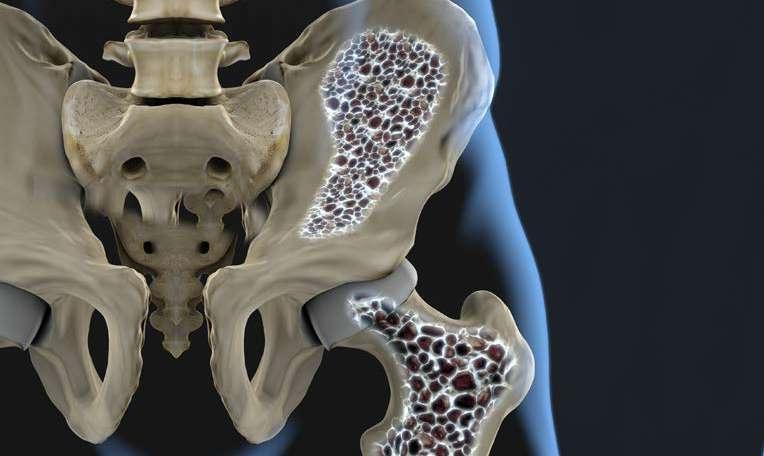

NO TE CAIGAS DEL BANQUITO

LA MANERA MÁS FRECUENTE EN QUE LAS PERSONAS DESCUBREN QUE SUFREN DE OSTEOPOROSIS ES POSTERIOR A UNA CAÍDA, COMÚNMENTE LA DEL BANQUITO, LA OSTEOPOROSIS ES ASINTOMÁTICA, LA MAYORÍA DE LAS PERSONAS QUE PADECEN ESTA PATOLOGÍA NO LO SABEN. Debido a que el 70% de las personas no presentan complicaciones evidentes como fracturas, si se pueden dar cuenta después de un accidente, por ejemplo, todos en casa tenemos un banquito, para alcanzar las superficies que superan los 2 metros de alto, aquellas donde solemos guardar las cosas que diariamente no usamos, algunos adornos, maletas, trajes especiales, joyería, entre otros.

Una caída por inestabilidad, por un paso en falso puede costarle una fractura y largos meses de terapia.

¿POR QUÉ APARECE LA OSTEOPOROSIS?

1. Factores genéticos

2. Baja ingesta de calcio en la dieta

3. Baja ingesta de Vitamina D

4. Sedentarismo

5. Alcoholismo

6. Tabaquismo

La aparición de esta patología se encuentra con más frecuencia en las mujeres posmenopáusicas, debido a la descalcificación por el proceso hormonal, pero también puede afectar a hombres y personas más jóvenes.

La osteoporosis es asintomática, en su mayoría las personas que padecen esta patología no lo saben. Esta condición suele ser diagnosticada por medio de exámenes ya sean preventivas o indicadas por diversas molestias de salud.

Esta enfermedad se caracteriza por la disminución en la densidad ósea, afectando su calidad y generando una alteración en la micro arquitectura de los huesos, causando fragilidad ósea mayor, lo que hace que los huesos sean propensos a fracturas por caídas menores o movimientos bruscos que en una persona sana no generarían estas consecuencias. Las lesiones más comunes en los pacientes con esta condición son: fractura de fémur o de cadera, fractura de muñeca y fractura de columna vertebral.